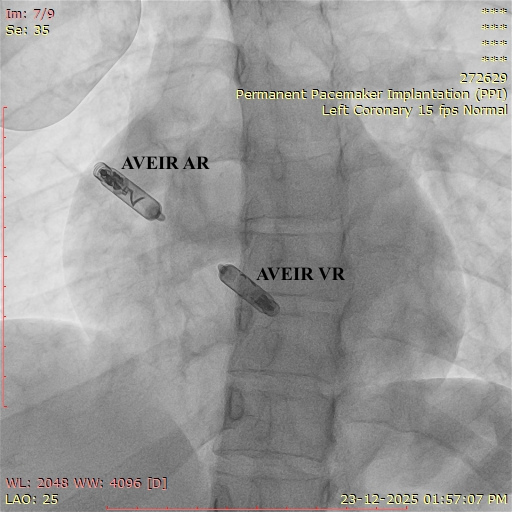

- Pacemaker & ICD Implantation

Most leadless pacemakers last between 8 to 12 years, depending on your heart’s needs and device programming.

Yes. While designed to stay in the heart permanently, it can be turned off or removed and replaced if required.